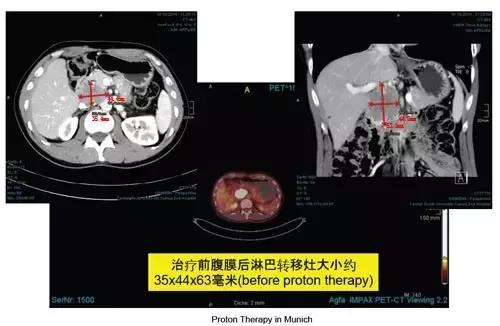

二、腹膜后淋巴结转移,患者男性42岁。

病历诊断:

2013年1月诊断出胆囊腺癌后进行胆囊与周围肝脏的切除,手术后做了四次化疗,2014年10月PET/CT检查发现下腔静脉和胰脏之间有一淋巴转移灶。

质子治疗:

德国慕尼黑质子中心(RPTC)

治疗时间:2015年11月~12月

用法剂量:淋巴转移灶施予20x3.0Gy(RBE),一周五次,总剂量60.0Gy(RBE);

腹部后整个区域淋巴施予20x2.5Gy(RBE),一周五次,总剂量50.0Gy(RBE);每周进行一次同步化疗(Gemcitabine),共做了三次。

副作用与治疗结果:

治疗第三周时病人感到背部与上腹疼痛、因为化疗的关系偶尔觉得恶心且容易便秘,因为白血球与血小板稍低,有一周的化疗没有做。治疗完9个月后再次进行CT检查,腹膜后淋巴转移灶已经完全消失,此外未发现有其他的转移。

质子治疗剂量分布图:

治疗前后影像对比: